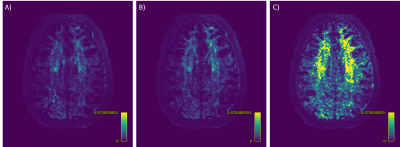

Figure 5: The SSE error between the ground truth SH coefficients and the coefficients predicted by: A) SDNet, B) FODNet and C) MSMT CSD, for slice 72, subject 13821 from the HCP.